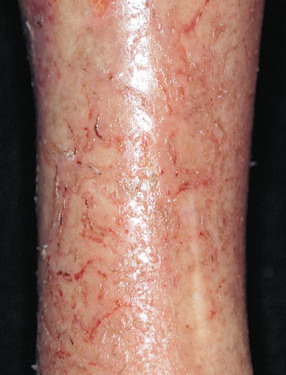

Eczema Craquelle or Asteatotic eczema as it is sometimes called, occurs in older people who have a tendency to have thinner and dryer skin. The word Craquele is a French word meaning, “covered with cracks”, as seen on the surface of old china. It was first described by the French dermatologist Brocq in 1907. This is also known as asteatotic eczema and it occurs in older people who have thinner and dryer skin. In Eczema Craquelle, Large dry scales may form on the skin giving a “crazy-paving” appearance to the skin. It’s often worse in winter and appears on the legs, arms, and hands. Eczema Craquele is characterized by dry, cracked, fissured skin and redness. It is extremely common in communities of elderly people and may be triggered by soap remaining on the skin after a bed bath. Using a good moisturizing routine and switching from soap to a cleansing bar for dry sensitive skin (such as Cetaphil “moisturizing gentle cleansing bar or Dove) can alleviate it. Steroid creams are generally best avoided because the underlying skin is already very thin and delicate.

Eczema Craquele occurs in older people who have thinner and dryer skin. Eczema Craquele occurs more often in winter and appears on the legs, arms, and hands. It is characterized by dry, cracked, fissured skin and redness. Large dry scales may form on the skin giving a “crazy-paving” appearance to the skin.